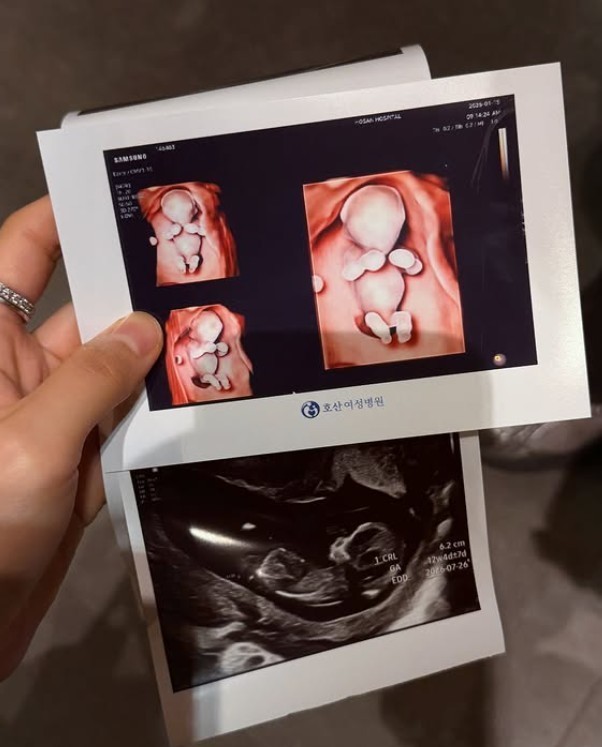

위키트리최근 방송된 동상이몽 시즌2-너는 내 운명에서는 결혼 2개월 차 신혼부부 김지영·윤수영의 일상이 공개됐다. 두 사람은 임신 초기 태교를 어떻게 받아들일 것인지를 두고 자연스럽게 의견 차이를 드러냈다.